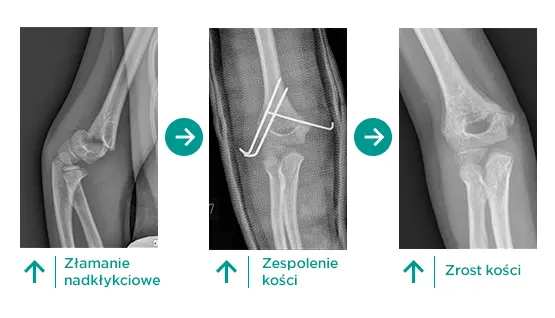

Spośród szerokiej gamy urazów, do jakich może dojść w trakcie skakania na trampolinie, złamania okolicy stawu łokciowego należą do najczęstszych i najcięższych. 75% złamań okolicy stawu łokciowego u dzieci stanowią właśnie złamania nadkłykciowe. Powstają one w wyniku upadku na wyprostowaną kończynę. Złamania nadkłykciowe dotyczą zarówno młodszych dzieci, jak i nastolatków, choć szczyt ich występowania przypada na wiek między 5. a 7. rokiem życia. Dlaczego są szczególnie niebezpieczne? Ponieważ w ich wyniku bardzo często dochodzi do uszkodzeń nerwów w okolicy stawu łokciowego, a odsetek niedowładów w tym przypadku wynosi 10-15%. Złamania te niosą ze sobą również ryzyko uszkodzeń naczyniowych ze względu na bezpośrednie sąsiedztwo tętnicy ramiennej. Niepodjęcie w porę leczenia operacyjnego może skutkować uszkodzeniem tej tętnicy, w wyniku którego dochodzi do niedokrwienia mięśni i charakterystycznego ustawienia ręki – to tak zwany przykurcz naczyniowy Volkmanna.

O ile złamania ze znacznym przemieszczeniem są łatwe do zdiagnozowania, to te nieprzemieszczone mogą być niezauważone. Dlatego lekarz często wykonuje badania obu stawów łokciowych (zdrowej i chorej ręki pacjenta), aby móc je wnikliwie porównać i odnaleźć objawy uszkodzeń. Czasami w przypadku uszkodzenia kości w okolicy stawu łokciowego jedyną wskazówką dla lekarza jest wystąpienie tak zwanego objawu poduszeczki, czyli delikatnego przejaśnienia widocznego na zdjęciu RTG, oznaczającego obecność krwiaka w okolicy nadkłykciowej. Na podstawie badania rentgenowskiego lekarz ocenia stopień uszkodzenia i podejmuje decyzję o leczeniu.

Złamania nieprzemieszczone nie wymagają operacji. Kończyna zostaje unieruchomiona na okres 3-4 tygodni, w zależności od wieku dziecka. Po zdjęciu unieruchomienia prowadzona jest rehabilitacja mająca na celu poprawę zakresu ruchomości stawu łokciowego. Jeśli jednak badanie obrazowe wykaże złamanie z przemieszczeniem kości, wówczas lekarz podejmuje decyzję o operacji. Odbywa się ona w znieczuleniu ogólnym i polega na nastawieniu odłamów kostnych, a następnie wprowadzeniu do miejsca uszkodzenia drutów Kischnera. Są to cienkie i sztywne druty, które utrzymują nastawione odłamy we właściwej pozycji. Zazwyczaj mocowane są w kości przezskórnie, a lekarz monitoruje efekty pracy, wykonując w czasie operacji serię zdjęć rentgenowskich. Kiedy jednak nie da się nastawić złamania pod monitorem rentgenowskim lub gdy są objawy uszkodzenia tętnicy ramiennej, należy wykonać bardziej inwazyjny zabieg. Lekarz przecina skórę i dostaje się do szczeliny złamania oraz uszkodzonych naczyń. Nastawia złamanie i uwalnia tętnicę. Również w przypadku leczenia otwartego stabilizacja polega na wprowadzeniu drutów Kirschnera. Po leczeniu operacyjnym także stosuje się unieruchomienie na okres 3-4 tygodni. Potem prowadzona jest rehabilitacja.